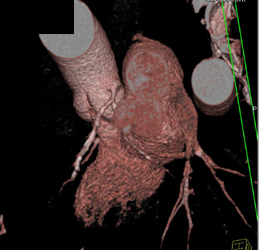

Calcified Bicuspid Valve